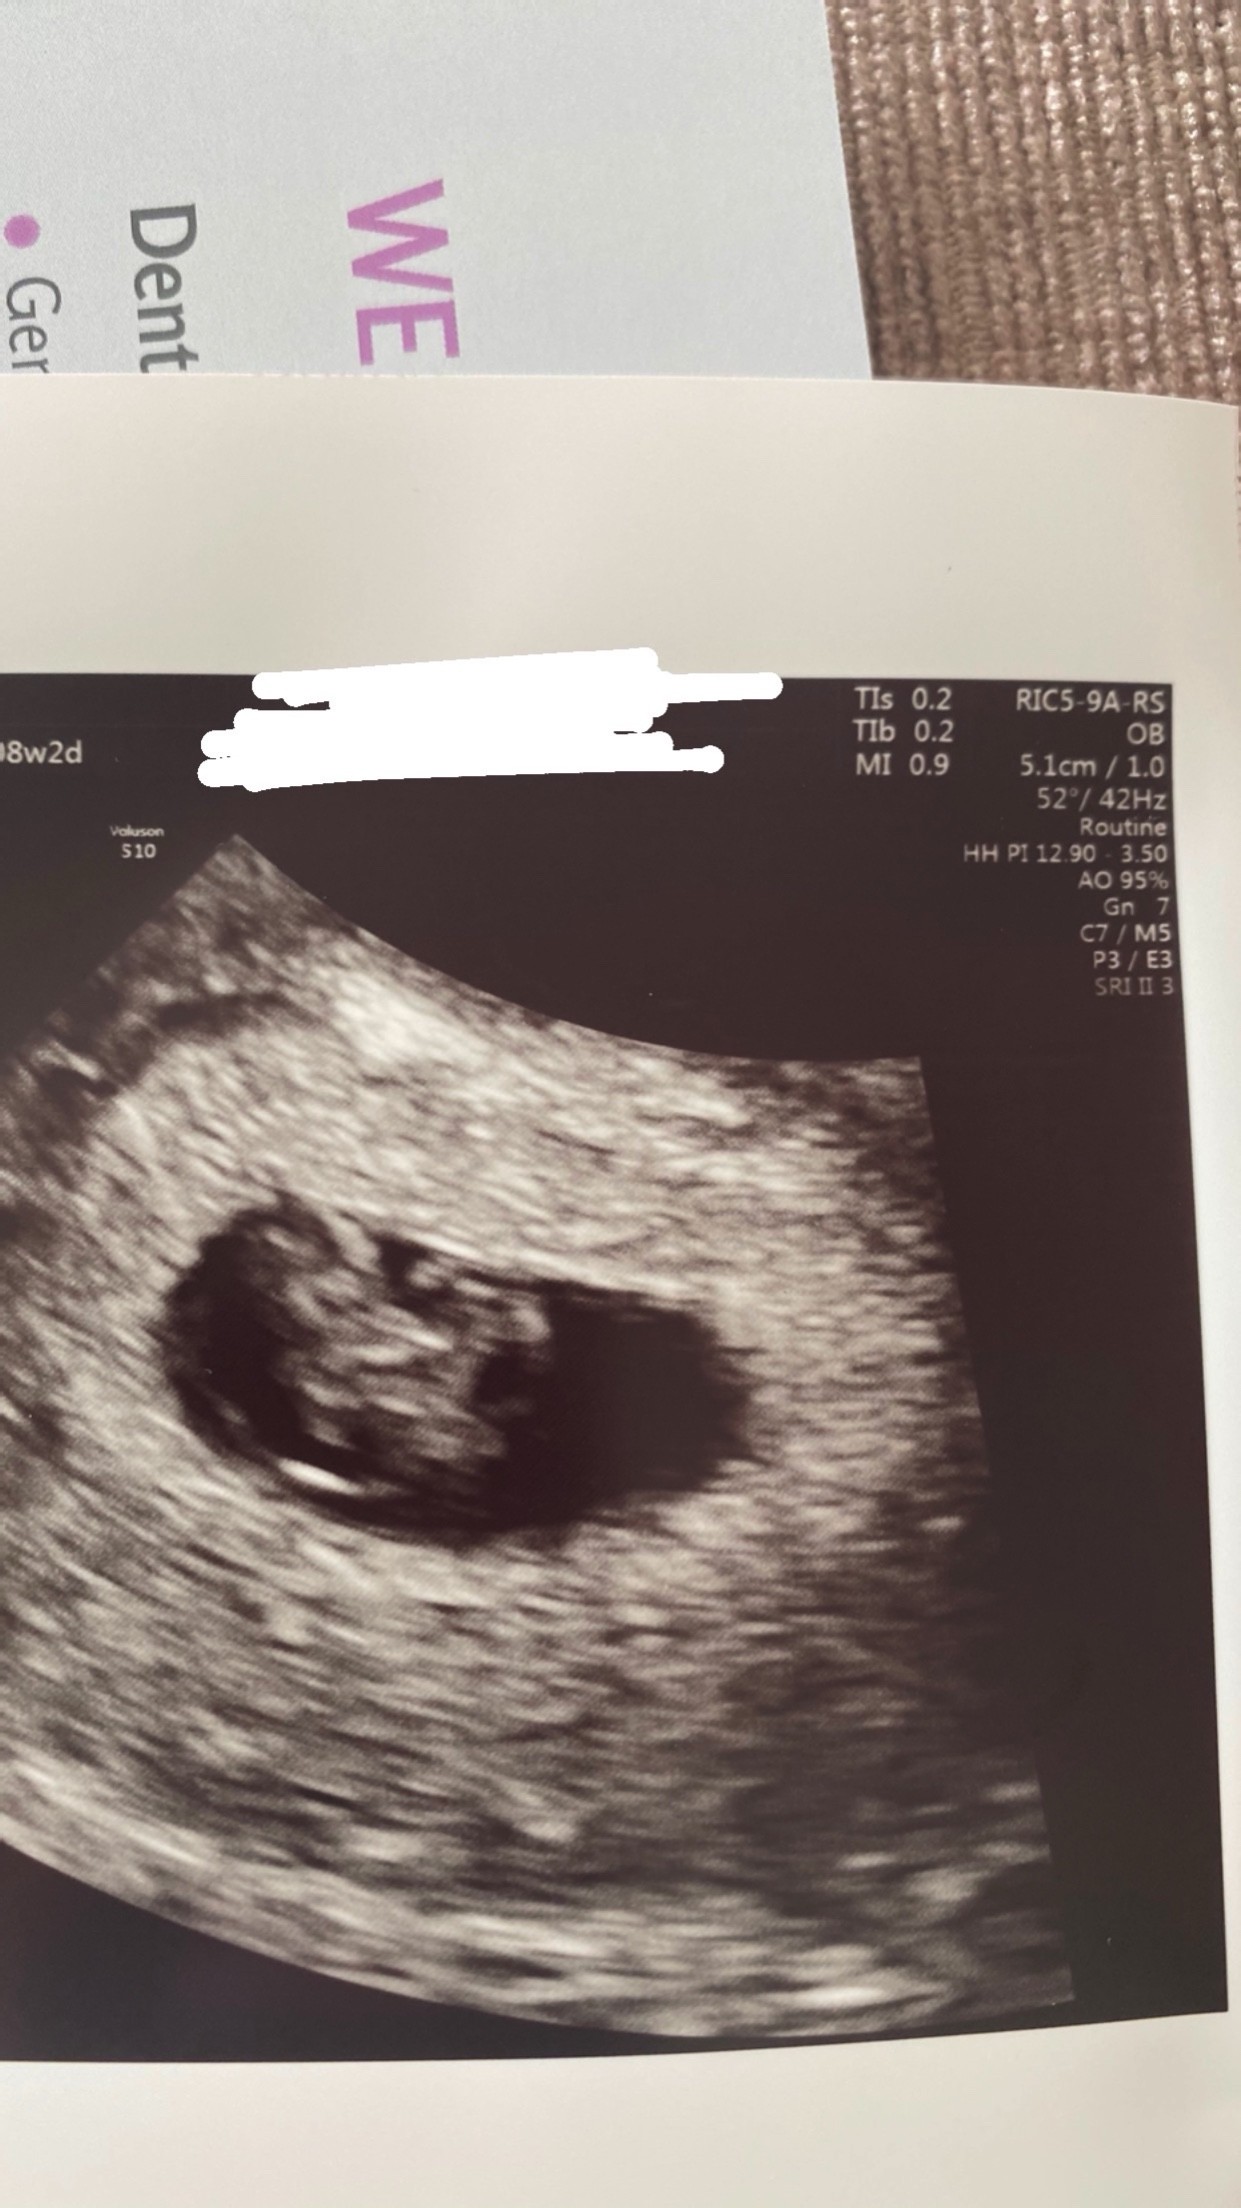

Zapomniałam wam wstawić zdjęcie mojej fasolki z tamtego tyg ,ciężki miałam tydzień

Załączniki

• CF57EAC4-6503-450C-B97F-E7A6B62100AC.jpeg

CF57EAC4-6503-450C-B97F-E7A6B62100AC.jpeg

344,4 KB · Wyświetleń: 127